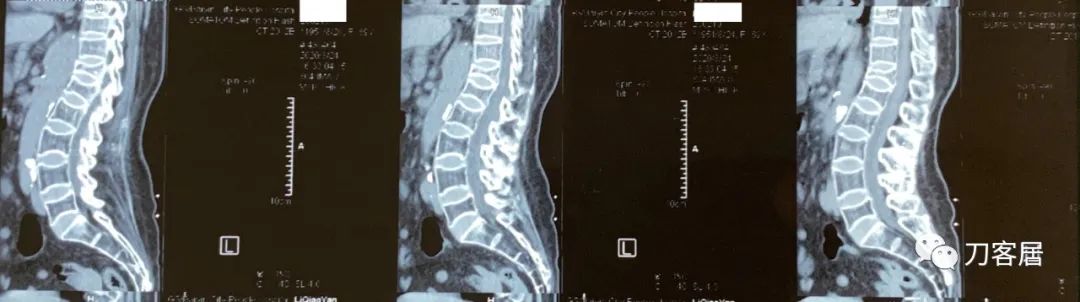

图08-20200824白银市人民医院腰椎CT

图09-20200824白银市人民医院腰椎CT